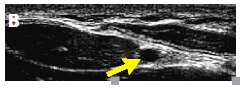

(2)穿刺部位的选择:保证探头在5~13 MHz的频率下开始评估血管。确保探头左侧所处部位的显影在屏幕左侧。自腕部起,对前臂侧面进行横向扫描,在桡骨茎及桡侧腕屈肌之间确定桡动脉及伴随静脉。必要时应用光压鉴别动脉及静脉(静脉是塌陷的,而动脉是充盈的),见图3。

图3.光压作用鉴别动、静脉

桡动脉(A,下方箭头)横断面可见有静脉伴随(白色箭头)。超声探头的光压可引起静脉塌陷但不影响动脉,动脉仍可见(B,箭头)